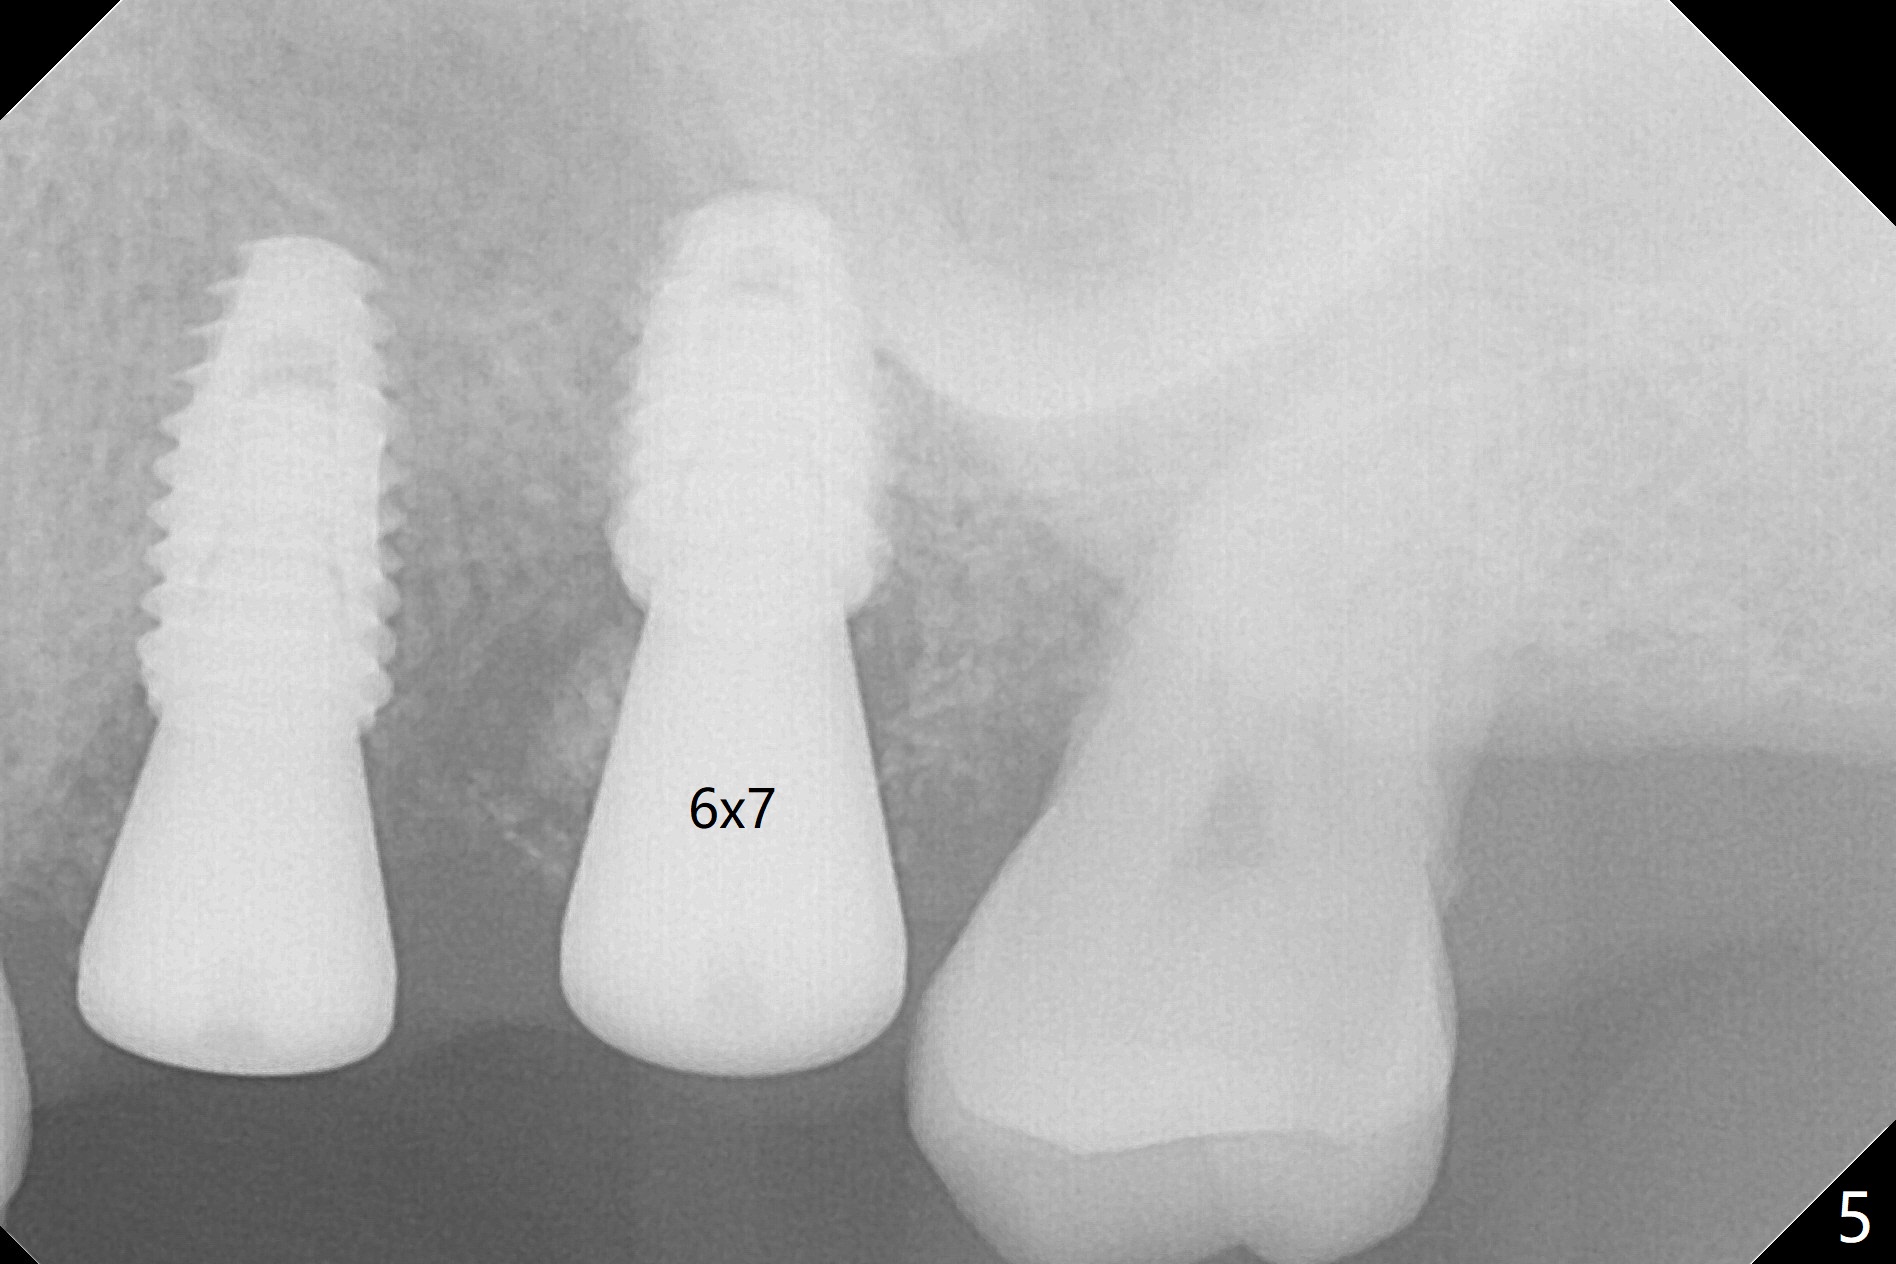

Six days later, "pain is less". Percussion of #13 healing abutment causes headache. There is no mobility at #13 or 14. The buccal gingiva is severely erythematous and edematous at #14. Chlorhexidine irrigation is conducted. After removal of the slightly subgingival healing abutment without pain, a 6x7 mm one is placed with severe pain. After local anesthesia, the implant seems to be mobile. The new abutment is advanced ~ 1 mm (Fig.5). Augmentin is prescribed. One week later there is no sign or symptom of infection. It appears that Augmentin should be prescribed after sinus surgery. The implant at #14 is removed with bone graft 1 month post placement. The graft appears to heal 4 months post implant placement (Fig.6,7 (5 months post placement at #13)).